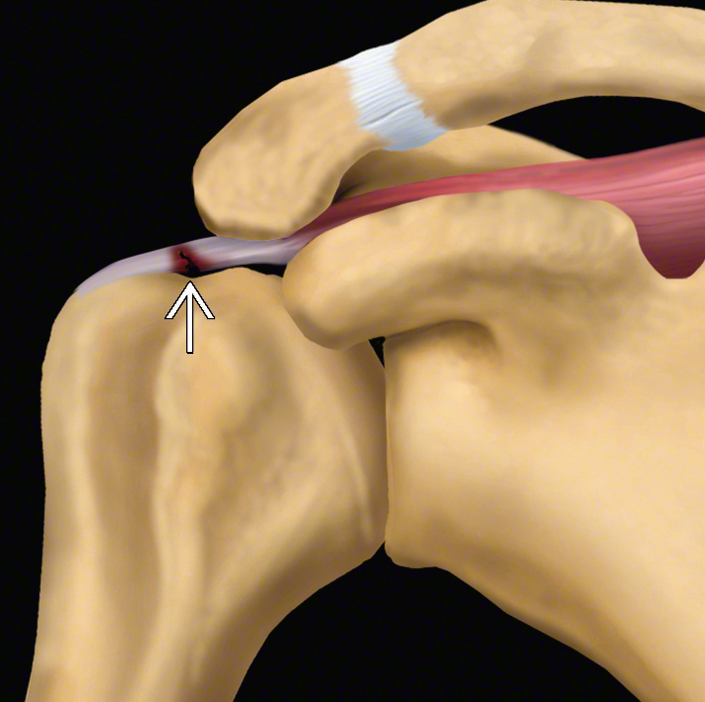

![]() |

| Rotator manşet yırtığının A. Şematik çizimi, B. MR görüntüsü | |